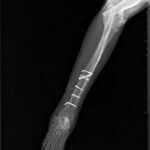

Dijagnoza se postavlja rendgenskim snimkama koje pokazuju lokaciju i tip prijeloma.

Liječenje može biti konzervativno, pomoću gipsa ili udlage, ili kirurško, uključujući pločice, vijke, čavle ili vanjsku fiksaciju.